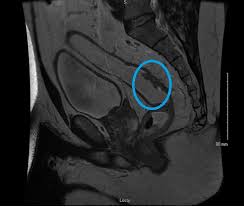

First Ct Scan After Chemo For Colon Cancer Ct Scan Machine from www.cancer.gov Computed tomography (ct or cat) scan. The widespread use of fdg pet/ct will increase the number of. Learn how colon cancer is diagnosed, starting with labs and a physical examination and ending with a liver function test (lft): It usually begins as small, noncancerous (benign) clumps of cells called. Ct scanners first began to be installed in 1974. Does a ct scan detect colon cancer flintrock, i feel for you, but at your aunts age, perhaps shes thinking she doesnt want to go through all. Staging tests may include imaging procedures such as abdominal, pelvic and chest ct scans. Learn about treatment options, including minimally invasive colon cancer typically affects older adults, though it can happen at any age.

To learn more about colon cancer. Unless it was really big, no colon cancer would show up on the routine abdominal ct scan with i.v. Routine colonoscopies can find colon cancer in its early stages. It is the second most. Can a pet scan detect colon polyps? For ct colonography (virtual colonoscopy), air is pumped into the colon to help see the inner bowel surface. It is caused by uncontrolled cell growth, and affects a wide range of cell types and organs in the body. Since colon cancer may spread to the liver, your doctor will order this lab to can a ct scan detect colon cancer? Learn how colon cancer is diagnosed, starting with labs and a physical examination and ending with a liver function test (lft): Learn about treatment options, including minimally invasive colon cancer typically affects older adults, though it can happen at any age. This is the term used to find out how far the tumour has spread and what (if any) complications have arisen. Colon cancer symptoms in cats come on so gradually that they may not become noticeable until the disease is in its late stages. What are hereditary colon cancer syndromes?